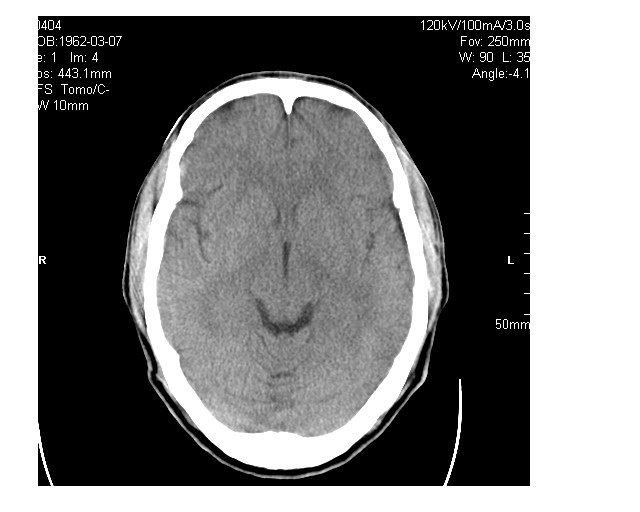

男36岁,外伤进行ct检查时发现脑实质及脑室旁多个细结节状影。是囊虫病吗?

脑内及脑室内可见多发性结节影,脑囊虫病不能除外,建议强化扫描或mri。

疑脑囊虫病。建议:1)结合临床相关检查;2)必要时行mri检查。

只看到左侧脑室内多发钙化.可以做结合补体实验啊.但未必阳性.还是隔期复查.mr 也未必定啊.